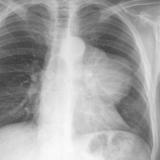

Case 8a Thymoma PA

Date: 03/27/2009

Views: 9448